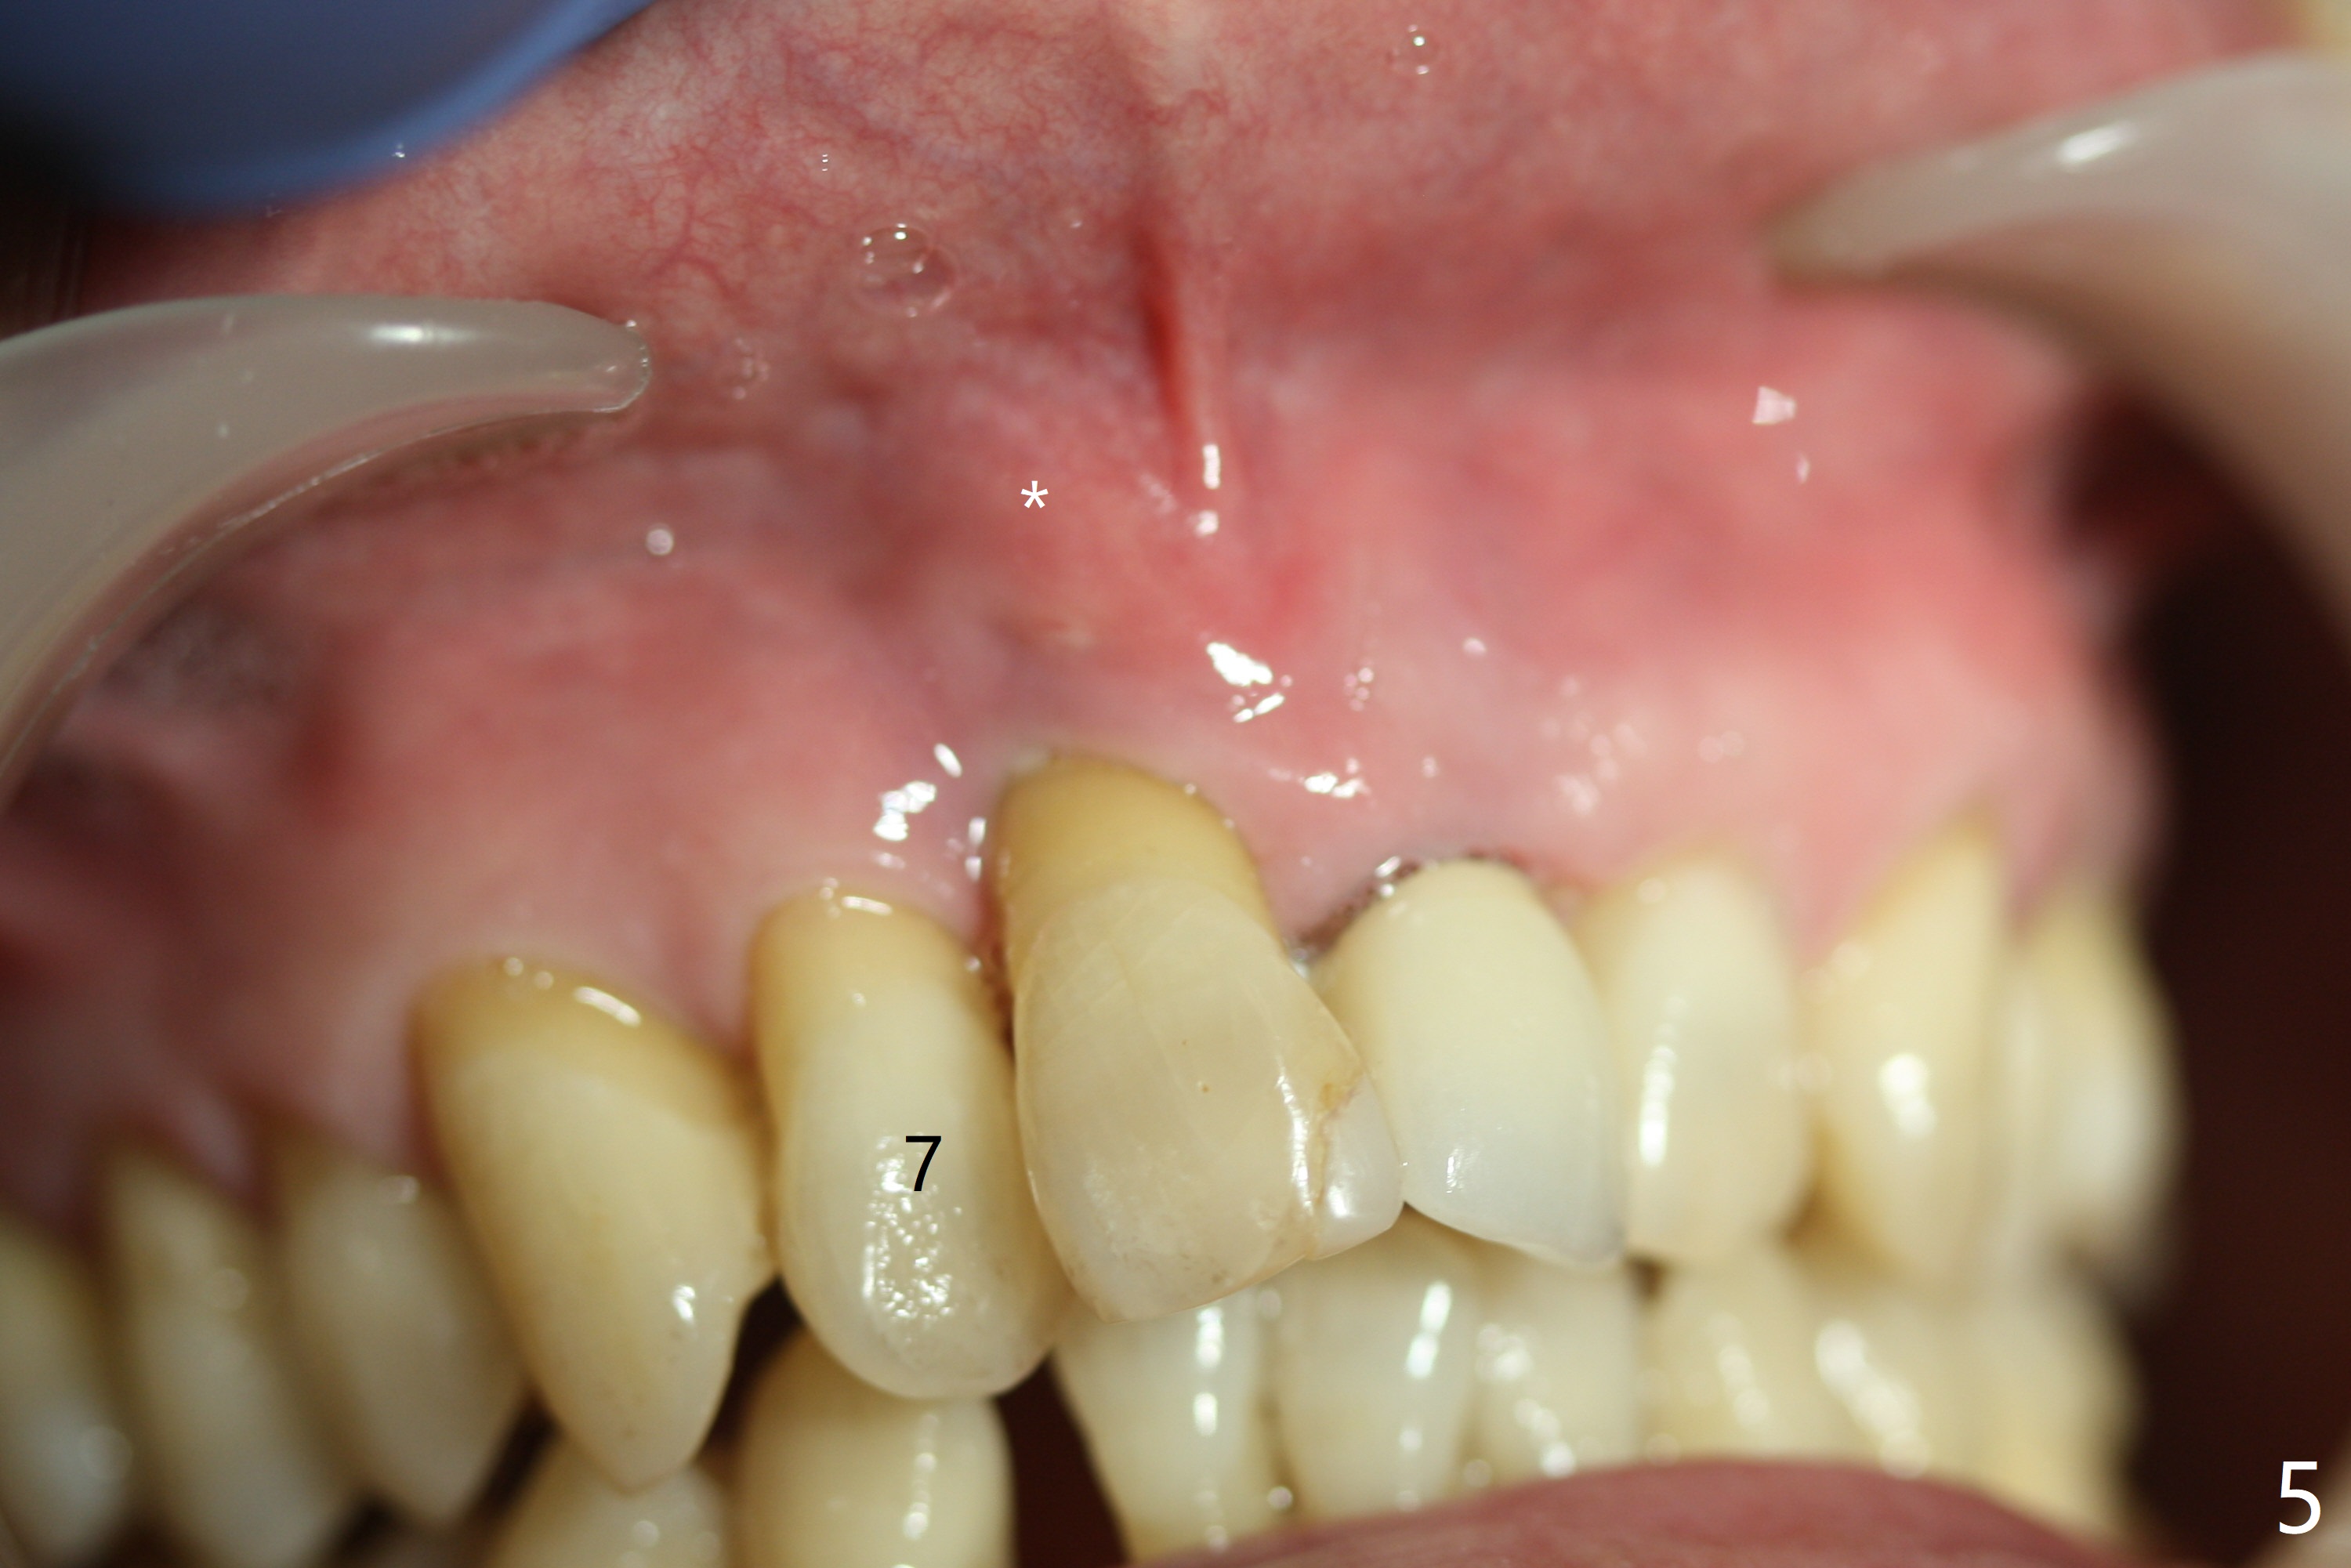

A 59-year-old man requests treatment for buccally displaced upper central incisors (Fig.1,2). It appears that the buccal plate is lost, but the bone height will allow placement of 3.5x13 mm implants with guide (Fig.3). Because of severe infection apical to the tooth #8 (Fig.4,5 *) and truncation of the incisal edges of the upper central incisors during CBCT taking (Fig.6,7 *), guided surgery may not be appropriate. The mesial surfaces of the teeth #7 and 10 and the incisal edges of the lower incisors (*) will be trimmed for immediate provisional. Immediate implants will be placed in the palatal crest of #8 (Fig.6 <) and close to the palatal crest of #9 (Fig.7). Angled abutments are expected (4.5x15 degree, A or B (4 mm cuff). PRF is to be preparedx2 (one for membrane; the other for sticky bone). Take Alginate impression when the patient returns for surgical stent.